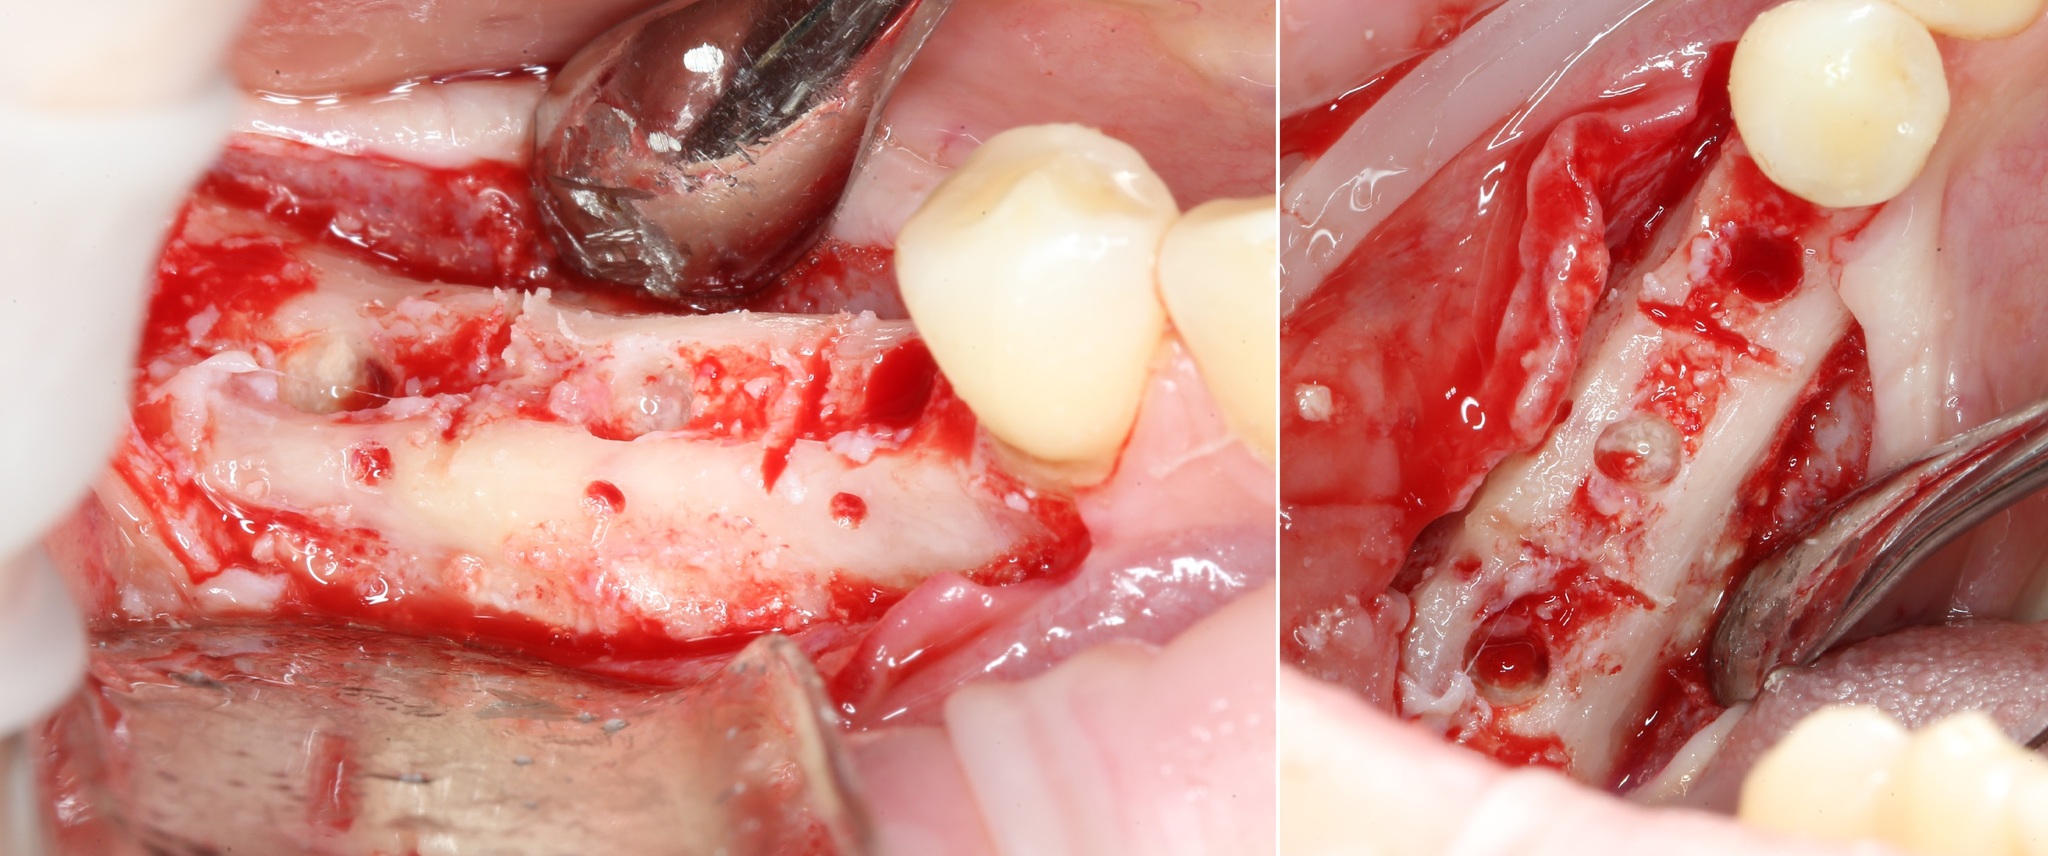

Всё тот же разрез и скелетирование кости:

Фиксирующие винты нам больше не нужны. Неровные костные края сошлифовываются при помощи того же прямого наконечника, но уже с твёрдосплавными шаровидными борами:

Выглядит это так: